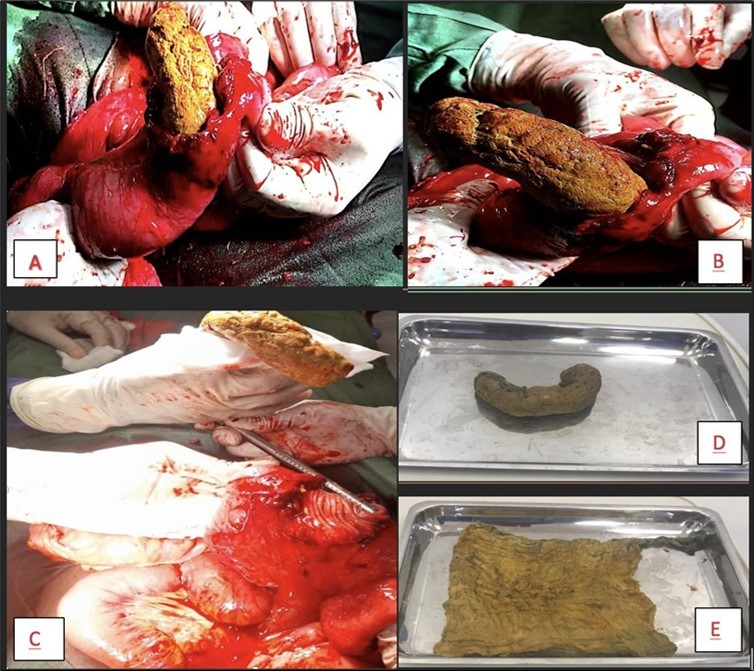

Intraoperatively, there was no free fluid in the peritoneum, dilated loops of small bowel were noted with adherence to the left lower quadrant of the abdominal wall. Adhesions were broken down and a firm intraluminal mass, approximately 20cm in length was noticed lurking out of the site of an iatrogenic injury made in the jejunum from the adhesiolysis. This was easily milked out (Figure 3). A resection of 20cm of the jejunum was done with an end-to-end anastomosis.

Figure 3.A picture showing the intraluminal mass within the lumen of the jejunum (A) which was milked slowly out of the bowel (B). The defect in the bowel (C) is seen after the mass is completely out. The mass (D) was opened up to show its character (E), a surgical sponge.